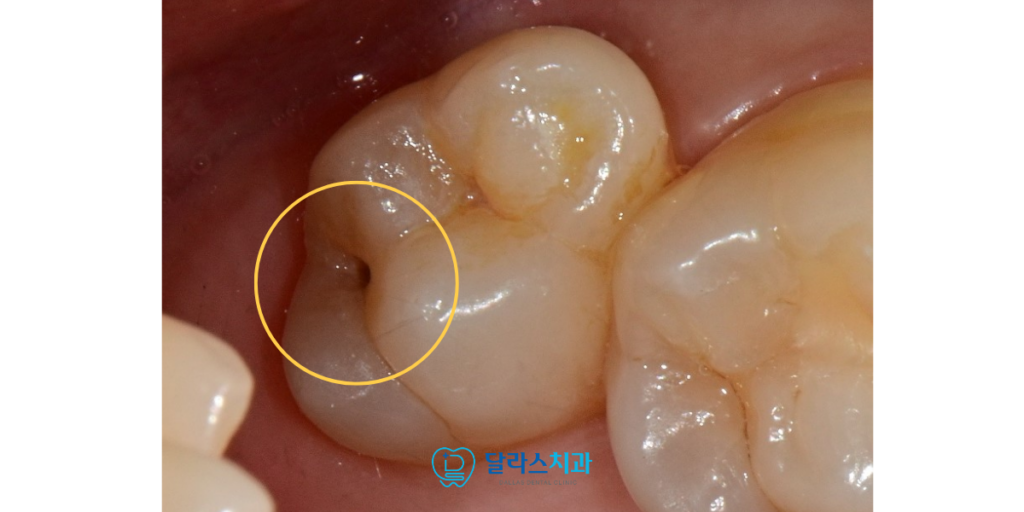

노원역치과 달라스치과에서 진행한 이번 증례는

치아의 씹는 면에 발생한 충치를 레진으로 수복한 사례입니다.

환자분께서는 정기검진을 통해서

기존의 작은 충치들은 관리를 하고 계시는 중이었습니다.

이번 정기검진에서 또한 별다른 통증을 느끼지 못하셨으나

충치가 보다 진행이 된 것을 확인하였습니다.

치료 전 2026.02.25

정밀한 진단 결과 충치는 법랑질을 지나 상아질의 얕은 부분까지 진행된 상태였습니다.

비록 환자분께서 일상생활에서 시린 증상을 겪지는 않으셨지만

상아질은 법랑질보다 충치 확산 속도가 빠르기 때문에

더 큰 손상을 막기 위해 즉각적인 치료를 결정하였습니다.

겉으로 보기에는 점상의 충치였으나 충치를 제거해보니 깊게 우식이 존재했습니다.